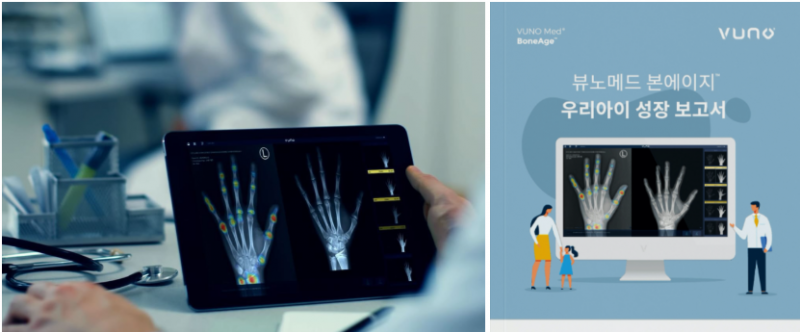

✔ 가장 기본적인 방법은 X-ray 촬영입니다.

보통 왼손과 손목 부위를 찍는데, 이 부위가 뼈의 성장 상태를 가장 명확하게 보여주기 때문이에요.

촬영 시간은 5분도 채 걸리지 않아서 아이도 부담 없이 받을 수 있어요.

요즘은 AI 기술을 활용한 성장판 검사도 가능해졌어요.

2016년 식약처 승인을 받은 국내 최초의 AI 의료기기가 바로 그 주인공인데요, 예전처럼 의사가 일일이 비교할 필요 없이 AI가 X-ray 영상을 빠르게 분석해줘요.

정확도도 높고, 기존보다 진단 시간이 약 40% 단축되었다는 결과도 있어요.

무엇보다 분석 결과를 그래프와 도표로 보기 쉽게 제공해서, 아이의 현재 상태와 예상 키까지 한눈에 파악할 수 있죠.

성조숙증, 저신장증 같은 문제도 초기에 발견할 수 있기 때문에 진단의 폭이 훨씬 넓어졌어요.